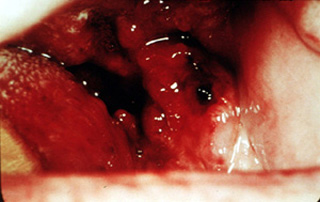

Crecimiento post exodoncia El área

de las exodoncias no cicatrizó (ver imagen anterior); y tres

semanas después había un crecimiento exofítico de apariencia

granular. |